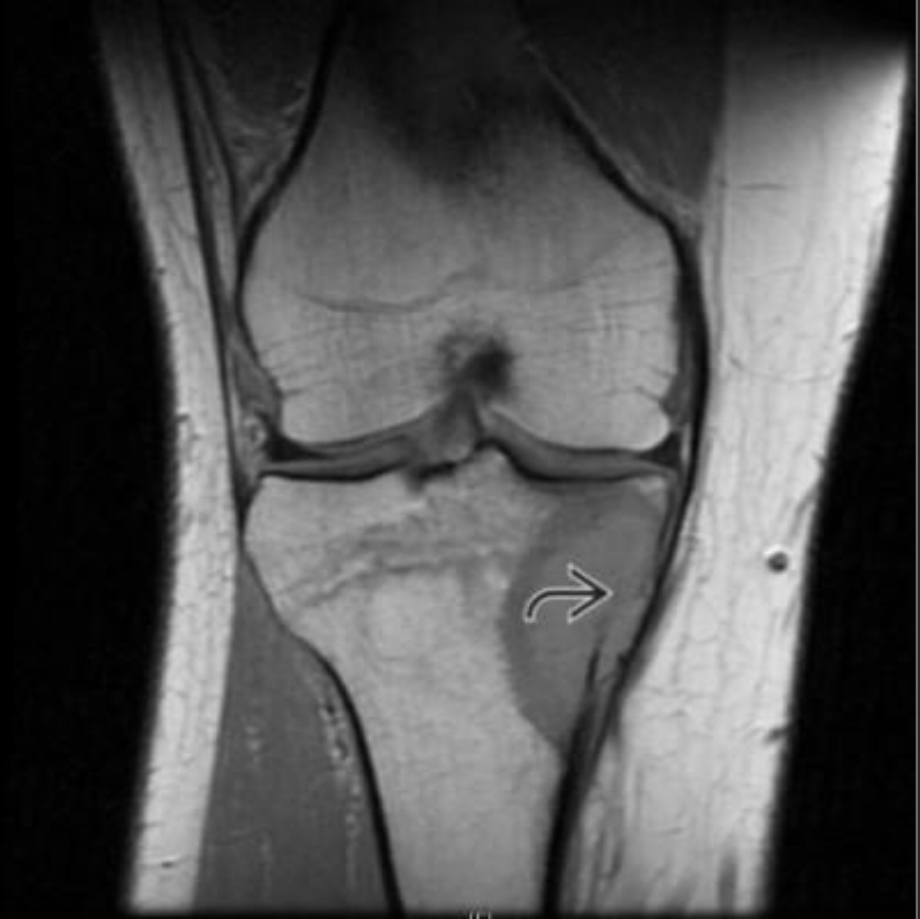

21M without trauma

Osteosarcoma.

with MR to help we see soft tissue extension and cortical breakthrough

Ewing and other small round blue cell tumors are also in diffx (or smoldering infx) but less likely based on age